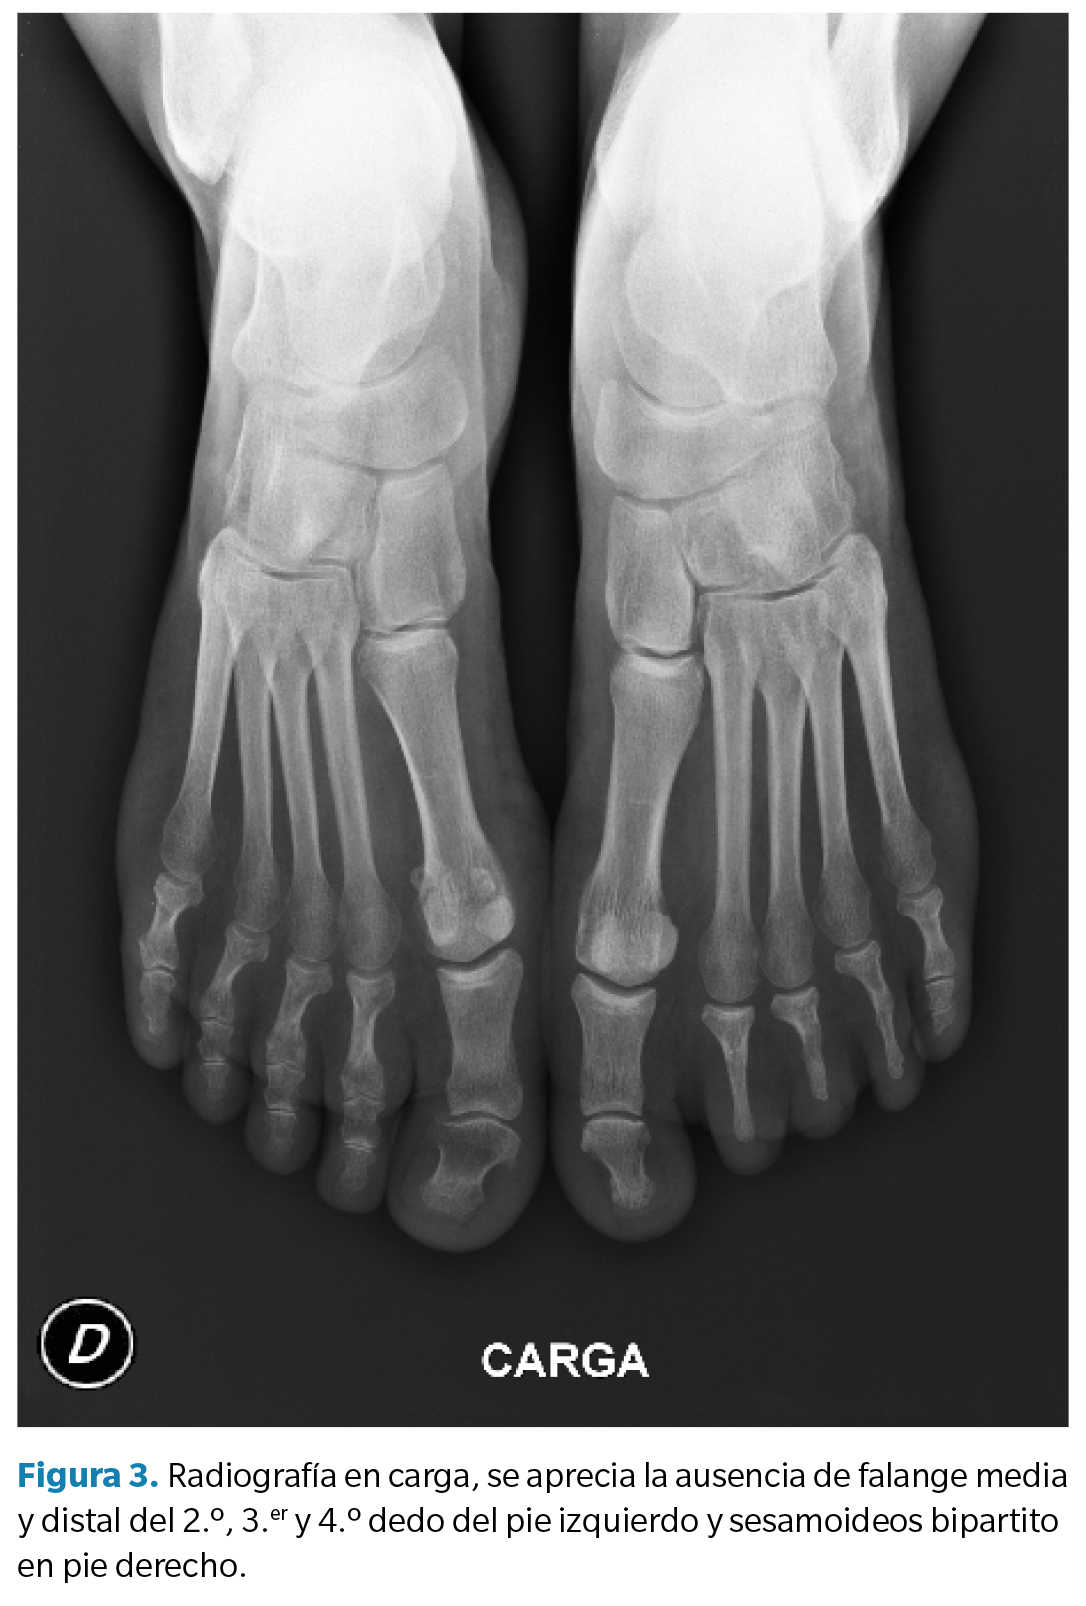

Posteriormente, se realizó una radiografía en carga, en proyección anteroposterior para complementar la exploración. Se halló de forma excepcional la ausencia de falanges medias y distales del segundo, tercero y cuarto dedo del pie izquierdo (Figura 2 y Figura 3). Se observó una diferencia de la fórmula metatarsal entre ambos pies, presentando un índex minus en el pie izquierdo y un index plus minus en el pie derecho. Hallazgos compatibles con BDB aislada.